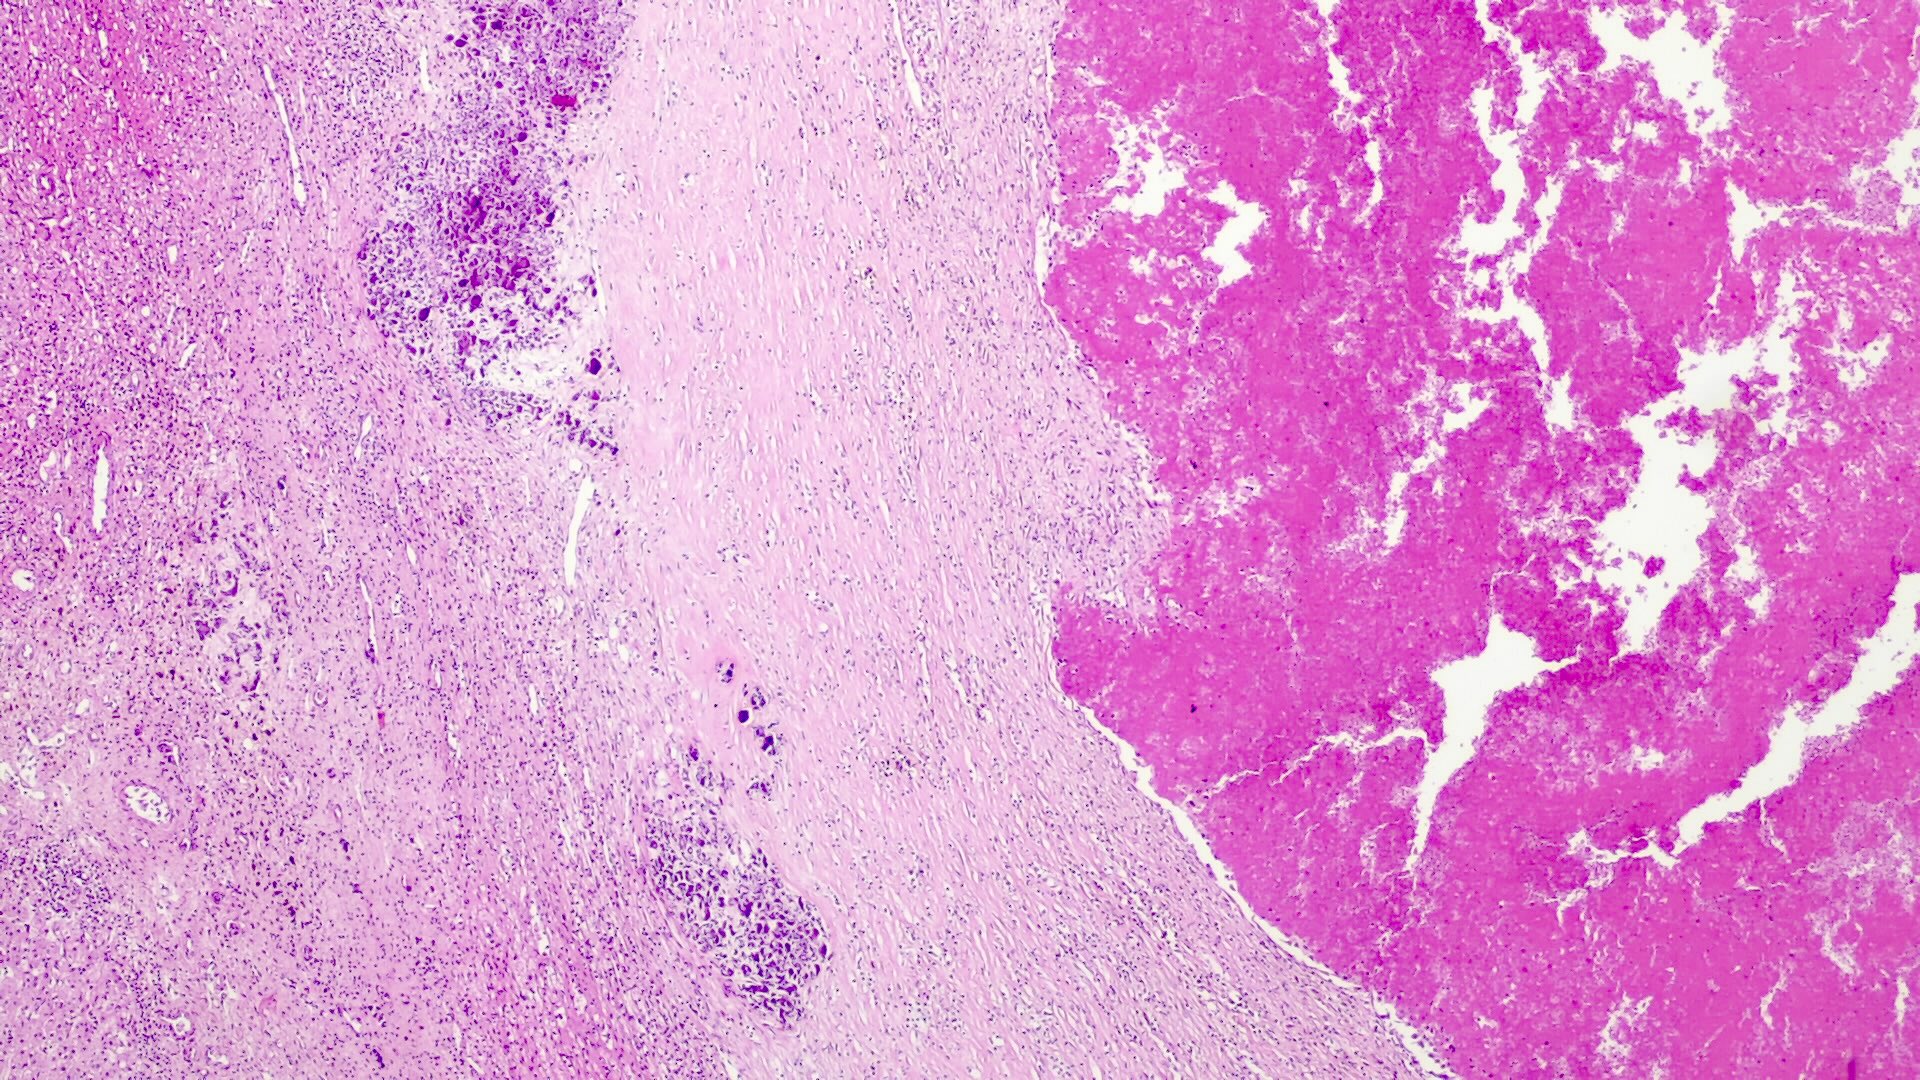

Gross description

- Single or multinodular tumor

- Well defined boundaries

- Tumors usually exhibit a tan-brown cut surface, especially in the fetal subtype (Medicine (Baltimore) 2018;97:e9647)

- Small cell undifferentiated subtypes have a variegated appearance

- Necrosis and hemorrhage are present in posttreatment specimens

- If osteoid is present, the texture is firm and gritty

Microscopic (histologic) description

- Classified by the International Pediatric Liver Tumor Consensus Classification as epithelial or mixed epithelial and mesenchymal

- Epithelial hepatoblastoma may exhibit several patterns (alone or in combination): fetal, embryonal, small cell undifferentiated (SCUD), cholangioblastic and macrotrabecular (J Gastrointest Oncol 2018;9:326)

- Fetal pattern (Pediatr Dev Pathol 2020;23:79)

- Thin trabeculae or nests of small to medium sized cells resembling hepatocytes of the developing fetal liver

- Clear or finely granular cytoplasm with variable amount of glycogen and lipids

- Small round nucleus with indistinct nucleolus

- Foci of extramedullary hematopoiesis are usually present

- Typically has low mitotic activity, referred to as well differentiated hepatoblastoma

- A subset has increased mitotic activity, with decreased cytoplasmatic glycogen and pleomorphic nuclei, referred to as mitotically active hepatoblastoma

- Embryonal pattern (Pediatr Dev Pathol 2020;23:79)

- Resembles the developing liver at 6 - 8 weeks of gestation

- Solid nests or glandular / acinar morphology, with papillae and pseudorosettes

- Dark and granular cytoplasm without glycogen or lipids

- Enlarged nuclei with coarse chromatin, resembling blastemal cells

- Extramedullary hematopoiesis is usually absent

- Increased mitotic activity

- Small cell undifferentiated pattern (Pediatr Dev Pathol 2020;23:79)

- Solid sheets of discohesive small cells (small, round blue tumor)

- Abundant mitoses, apoptosis and necrosis

- Macrotrabecular pattern

- Thick trabeculae (5 - 12 cells thick)

- Trabeculae may be composed of fetal, embryonal, pleomorphic or hepatocellular carcinoma-like cells

- Cholangioblastic pattern

- Small ducts within or around hepatocellular components

- Mesenchymal pattern (Pediatr Dev Pathol 2020;23:79)

- Mature and immature fibrous tissue

- Osteoid or osteoid-like tissue (more abundant after chemotherapy)

- Hyaline cartilage

- Small subset may exhibit teratoid features: endodermal, neuroectodermal (neuronal cells, glial tissue, melanin producing cells) and complex tissue (striated muscle)

Microscopic (histologic) images